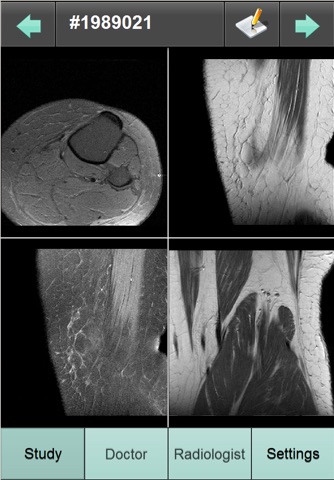

Cette application permet de consulter ses résultats dimagerie (images et compte rendu) en mettant en oeuvre une connexion sécurisée avec un serveur SYNAPSE Wave hébergé au sein la structure radiologique équipée, ayant réalisé lexamen radiologique.

Dans longlet Examen :

- Renseignez le numéro dexamen et le mot de passe associé pour accéder aux images de lexamen et à son compte-rendu